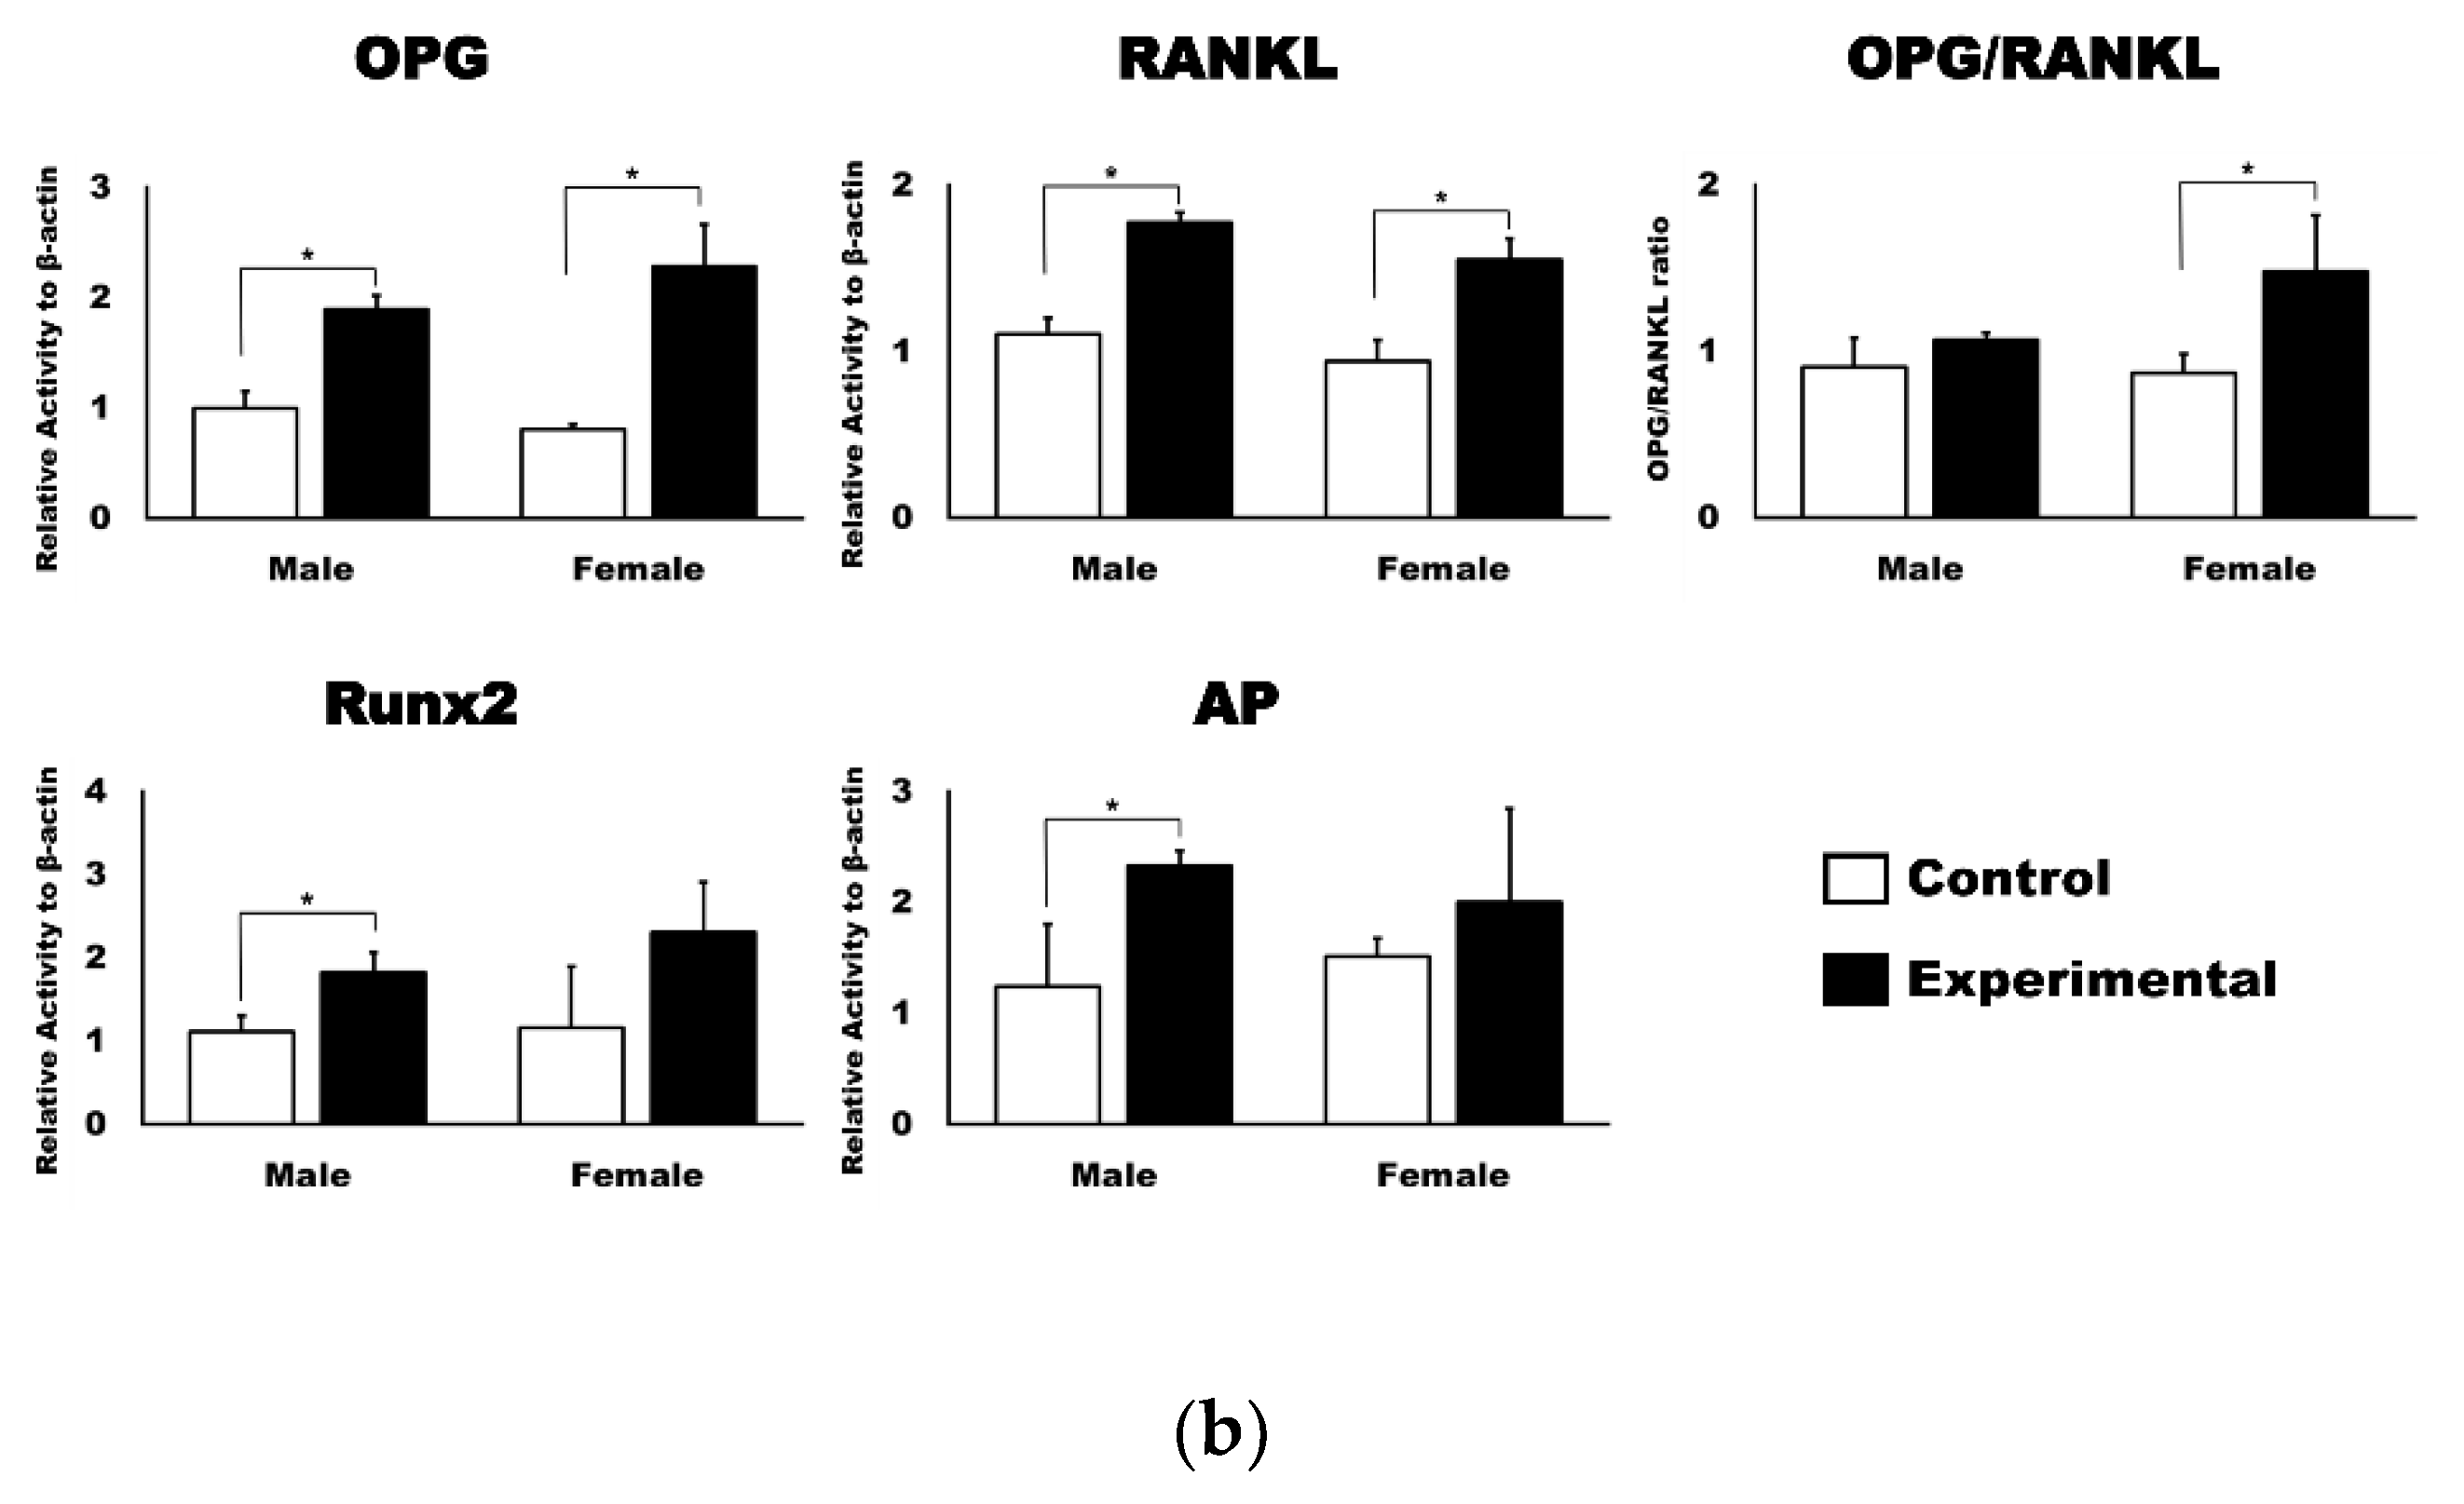

3.2. 4HR Increased OPG, RANKL, AP, and Runx2 Expression in Tissue